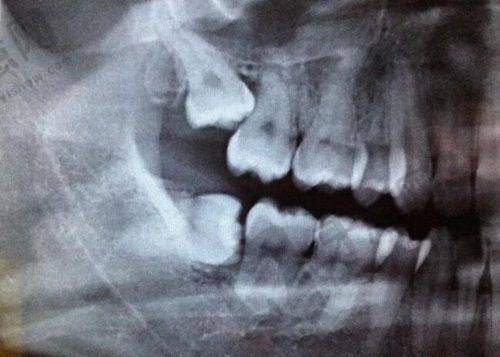

再说说种植牙。医院采用德国数字化Sirona CBCT设备和3shape口扫设备,实现了种植牙手术的数字化和精细化。医生可以通过三维口腔结构图像的展示,从任意角度观察分析患者病例,为种植牙手术提供精细的数据支持。这大大缩短了手术时间和周期,提高了患者的舒适度。医疗团队能熟练掌握各种种植牙技术,同样可以根据患者的具体情况制定个性化治疗方案。

在种植牙方面,医生们熟练掌握德国数字化Sirona CBCT设备和3shape口扫设备的使用,能够通过三维图像正确分析患者病例。他们精通各种种植牙技术,无论是单颗牙种植、多颗牙种植还是全口牙种植等复杂情况,都能游刃有余地处理。在手术过程中,凭借丰富的经验和精细的操作,大大提高了手术的成功几率和患者的舒适度。